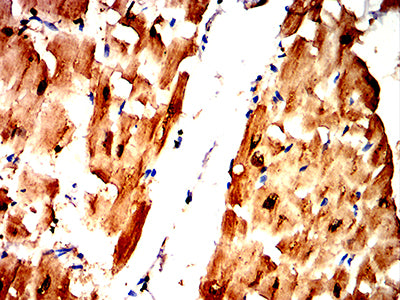

分类: 科研抗体货号: 32270别名: CMH2; RCM3; TnTC; cTnT; CMD1D; CMPD2; LVNC6应用: IHC,FCM反应种属: Human